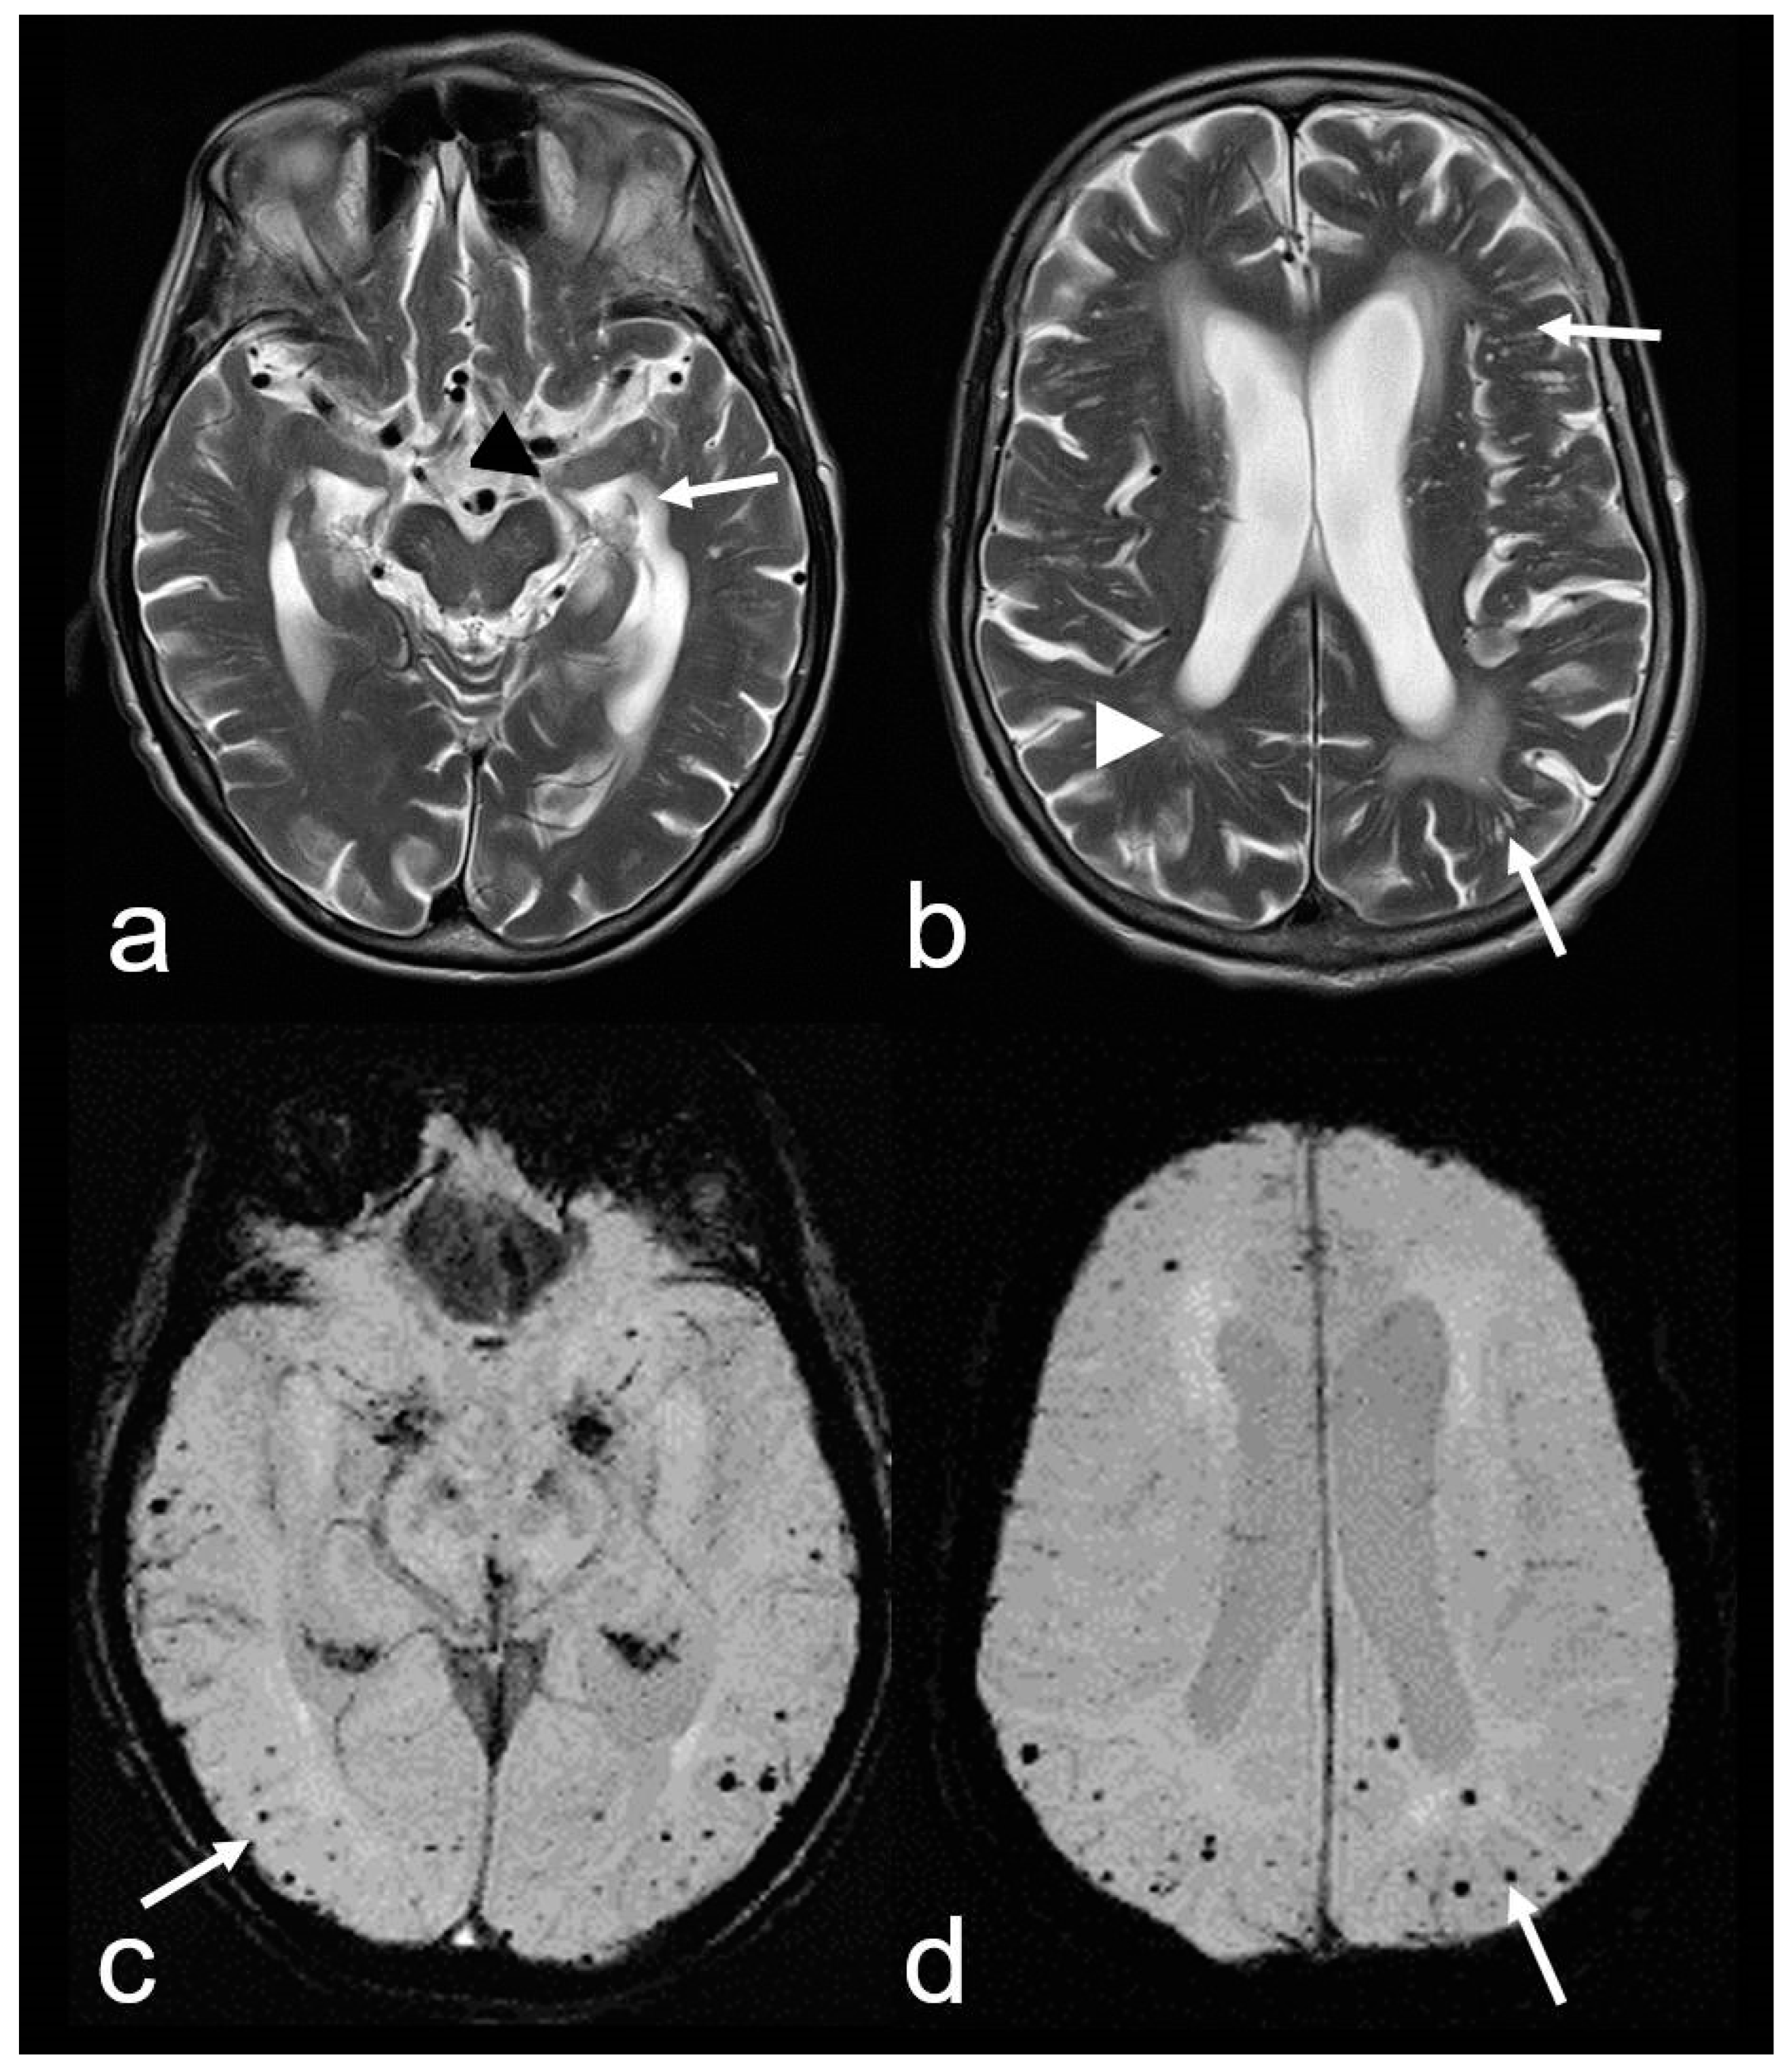

Figure 3.

Cerebral amyloid angiopathy (CAA) and Alzheimer’s disease (AD) in an 82-year-old woman with progressive cognitive decline and short-term memory disturbance. Axial T2-weighted images (WI) (a,b) showing distinct temporal mesial atrophy ((a), arrowhead), enlarged temporal horns ((a), arrow), vascular leukoencephalopathy ((b), arrowhead) and enlarged perivascular spaces (PVS; (b), arrow). Susceptibility-weighted imaging (SWI) ax. (c,d) disclosing multiple cortical and subcortical microbleeds (MB) (arrow), especially temporal and parietal; MRI 1.5 T Siemens AREA.